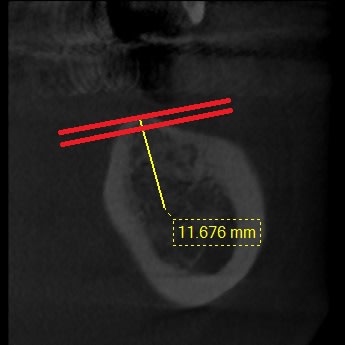

VOici la suite

Crete fine1 by6drq - Eugenol

Crete fne 2 lz2zwv - Eugenol

Coupe plus haute dpzgpt - Eugenol